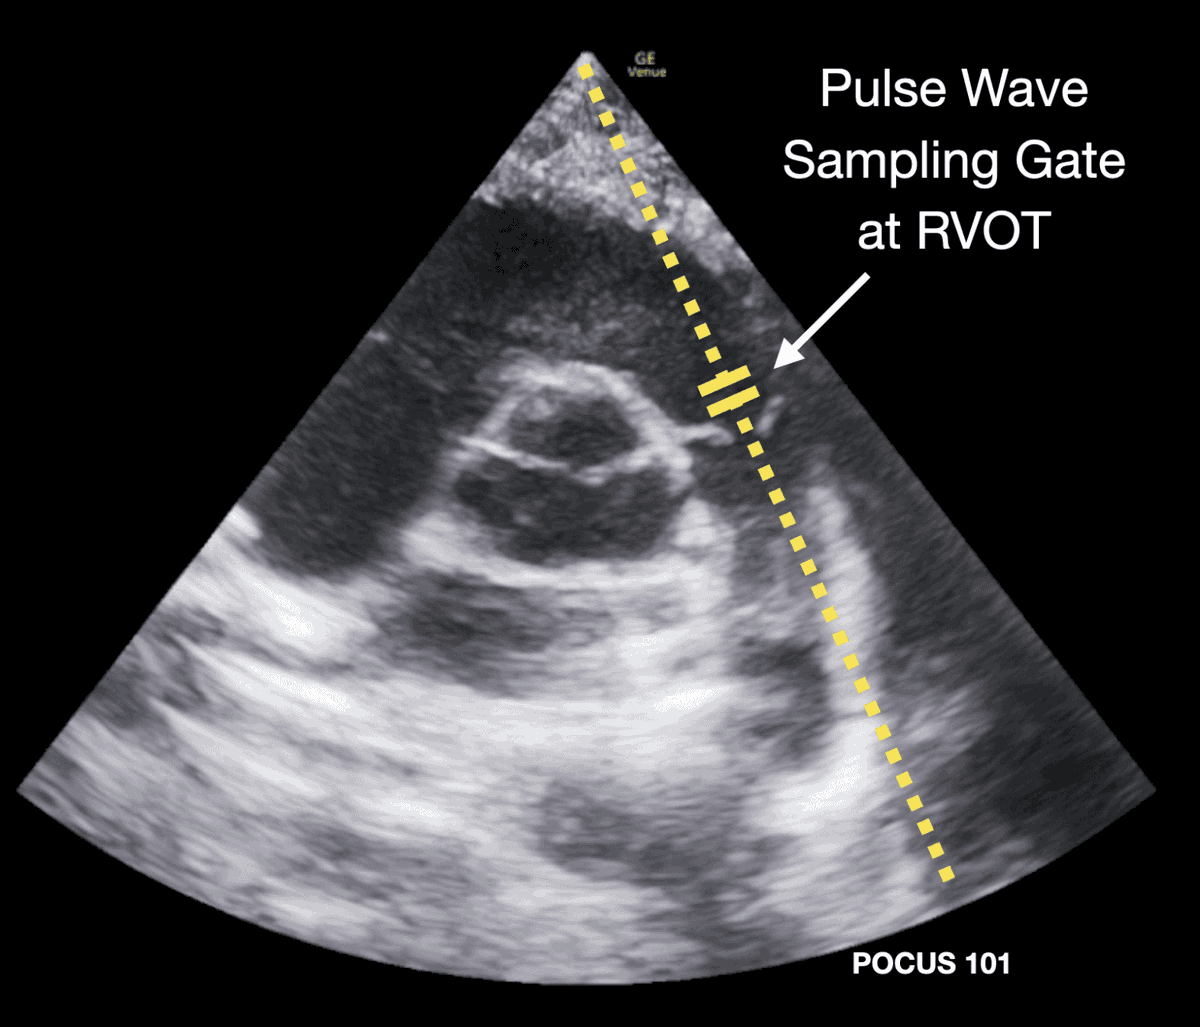

Pulmonary Artery Acceleration Time (PAAT)

■ Pulmonary Artery Acceleration Time (PAAT) is the time interval from the onset of systolic flow to the peak velocity of blood flow in the pulmonary artery, measured using pulsed-wave Doppler.

■ Physiological Meaning

● Reflects pulmonary vascular resistance (PVR).

● Shorter acceleration time = higher pulmonary artery pressure.

● Longer acceleration time = normal or low pulmonary pressures.

Normal: >130 ms

Borderline: ~100–130 ms

Mild Pulmonary Hypertension: ~60–100 ms

Severe Pulmonary Hypertension: <60 ms.

■ Why PAAT Shortens in Pulmonary Hypertension

In pulmonary hypertension (PH):

▪︎ Pulmonary artery pressure is elevated.

▪︎ RV faces increased afterload.

▪︎ Blood reaches peak velocity earlier.

▪︎ Doppler waveform becomes steeper and shorter.

Often associated with:

Mid-systolic notching (in advanced PH).

■ Clinical Importance

▪︎ Useful when TR jet is inadequate.

▪︎ Non-invasive estimate of pulmonary pressures.

▪︎ Correlates inversely with mean pulmonary artery pressure (mPAP).